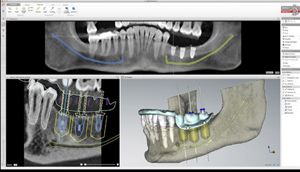

Implantología guiada por ordenador

Este nuevo avance que une la más alta tecnología radiológica, informática y quirúrgica nos permite en Multidental planificar las intervenciones de implantes dentales antes de hacerlas físicamente conociendo así de antemano y con máxima precisión, la posición exacta en la que podemos colocar el implante dental de acuerdo al hueso disponible del paciente.

Luego mediante un ordenador se fabrica una plantilla para ayudar a colocar los implantes dentales sin abrir la encía, un procedimiento que ahorra tiempo, nos permite en nuestra clínica dental, predecir el tratamiento y es definitivamente menos traumático para el paciente por ser minimamente invasiva.